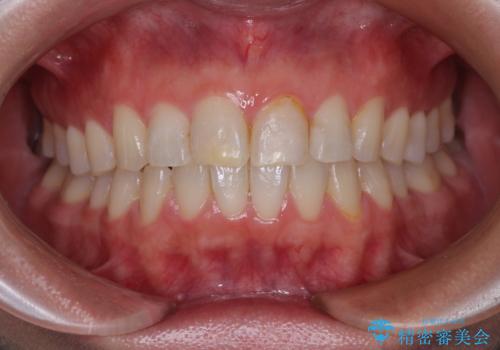

奥歯にインプラントを入れて銀歯もやり替えたい。

- ブリッジの歯のないところにインプラントを入れて、銀歯を白くやり替えたいと来院された患者様です。

歯の欠損している箇所にはインプラント治療をし、銀歯と仮詰めの部分はセラミックインレーにて補綴することとしました。